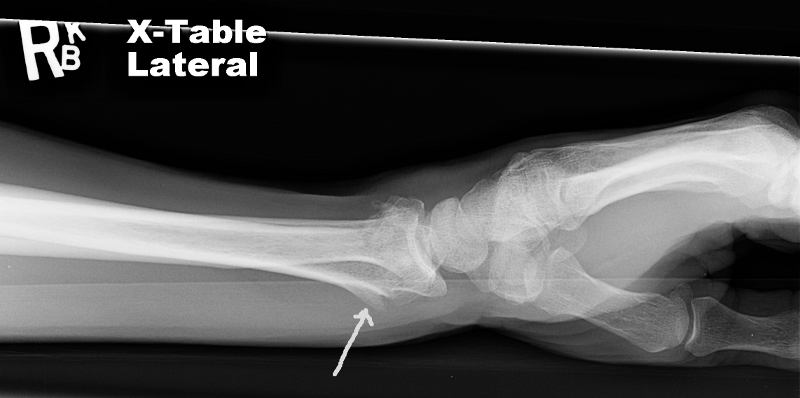

Tim Xray In August Tim fell off a truck while helping a friend move and broke both bones in his wrist. He healed fine and this winter he is doing more therapy, sawing and splitting 3 cords of wood.